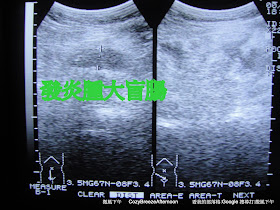

我一聽馬上有警覺心,不太像常見的 腸胃型感冒,可能是盲腸炎,於是請他躺在超音波檢查床上,壓他右下腹部的盲腸部位,果然有明顯壓痛,再做幾個盲腸炎的測試檢查:Psoas sign,Obturator sign,Rovsing’s sign,都呈現陽性,最後給他做腹部超音波檢查,右下腹部壓痛處有局部積水現象,雖然沒有找到腫脹的闌尾(AKA 盲腸), 局部積水很可能是急性盲腸炎產生的發炎分泌液體,柯先生得了急行盲腸癌的可能性非常高。

急性闌尾炎的診斷主要靠病史問診及身體觸診檢查,血液檢驗可能會發現白血球數升高,腹部X光有時候可以看到右下腹部有糞石及局部性的腸腫大現象。超音波可以用來輔助診斷,對於困難診斷之個案,可以使用電腦斷層掃描。急性闌尾炎的診斷率高達百分之八十至九十,但在某些人群中如孕婦、老年人以及嬰幼兒,其臨床症狀並不很明顯,在疾病的早期也不易被察覺,而在出現腹膜炎或敗血症時,才經由剖腹探測得知其闌尾已壞死穿孔。一般穿孔都發生在症狀出現後二十四至三十六小時,但小小孩或老年人可能會更早。闌尾穿孔後腹痛可能會從原先局限在右下腹變成整個下腹痛,但一般還是以右下腹較厲害。至於痛的程度每個人的耐受度都不一樣,很難做個說明,但小孩子不會表達,老年人對痛的耐受度高,故較難診斷。